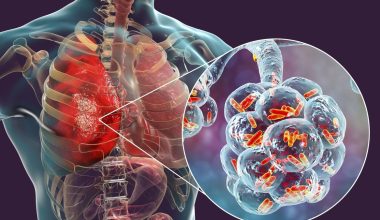

Στους πάσχοντες από στεφανιαία νόσο, το πάχος του Αχιλλείου τένοντα μπορεί να αποτελεί ένδειξη της σοβαρότητας της νόσου και πόσο πιθανό είναι να υποστούν έμφραγμα, σύμφωνα με νέα έρευνα.

Η μελέτη, που παρουσιάστηκε πρόσφατα στο συνέδριο της Αμερικανικής Ένωσης Καρδιολογίας, εξέτασε τη σχέση μεταξύ της σοβαρότητας της στεφανιαίας νόσου και του πάχους του Αχιλλείου τένοντα σε 241 άτομα που είχαν υποβληθεί σε εμφύτευση stent (μεταλλικό πλέγμα που εμφυτεύεται μετά την αγγειοπλαστική, γνωστή ως μπαλονάκι) σε στεφανιαία αρτηρία της καρδιάς με σκοπό να τη διατηρήσει ανοιχτή.

Οι ερευνητές διαπίστωσαν ότι το 80% όσων ο Αχίλλειος τένοντας είχε πάχος 9 χιλιοστά ή περισσότερο, είχαν πάνω από μία φραγμένες αρτηρίες και διέτρεχαν υψηλότερο κίνδυνο εμφράγματος.

Μεταξύ αυτών με λεπτότερο Αχίλλειο τένοντα, το 58% είχαν περισσότερες από μία φραγμένες αρτηρίες. Τα άτομα με παχύ Αχίλλειο τένοντα είχαν περισσότερες πιθανότητες στεφανιαίας νόσου, η οποία συνδέεται με υψηλότερο κίνδυνο εμφάνισης καρδιακών παθήσεων και θανάτου.

Ο επικεφαλής συγγραφέας της μελέτης, Δρ Takuya Hashimoto, καρδιολόγος στην Ιατρική Σχολή του Πανεπιστημίου Kitasato στο Τόκιο, δήλωσε ότι η διάγνωση του πάχους του Αχιλλείου τένοντα θα μπορούσε να χρησιμοποιηθεί για τον εντοπισμό ατόμων που κινδυνεύουν από καρδιακές παθήσεις.

Διευκρίνισε ωστόσο, ότι η παρούσα μελέτη δεν το επιβεβαίωσε, καθώς περιλάμβανε ασθενείς με στεφανιαία νόσο και όχι ασθενείς με πάχυνση του Αχιλλείου τένοντα λόγω άλλων αιτίων.

Άλλη μελέτη που παρουσιάστηκε στο συνέδριο, εξέτασε τον καλύτερο τρόπο διάγνωσης της οικογενούς υπερχοληστερολαιμίας μέσω της μέτρησης του πάχους του Αχιλλείου τένοντα.

Η οικογενής υπερχοληστερολαιμία είναι η πιο συχνή γενετική διαταραχή του μεταβολισμού. Η πάθηση οφείλεται σε κάποιο ελαττωματικό γονίδιο που κληρονομεί ένα άτομο από τους γονείς του με αποτέλεσμα να μην μπορεί ο οργανισμός να απομακρύνει την «κακή» (LDL) χοληστερόλη που κυκλοφορεί στο αίμα.

Η εναπόθεση και συσσώρευση κυττάρων πλούσιων σε χοληστερόλη σε διάφορα σημεία του σώματος, όπως στον Αχίλλειο τένοντα, κατάσταση γνωστή ως ξάνθωμα, αποτελεί γνωστό δείκτη πρόβλεψης στεφανιαίας νόσου σε άτομα με οικογενή υπερχοληστερολαιμία.